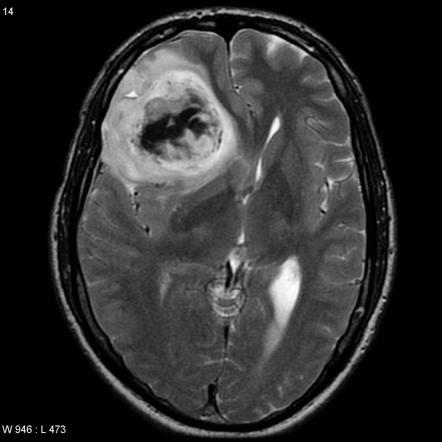

1. Estudios radiológicos:

1. Muestran efecto de masa, así como cambios en el encéfalo adyacente al tumor, como edema. Astrocitomas de alto grado - - - > vasos anómalos que están agujereados y por ello muestran refuerzo con contraste en los estudios de imagen.